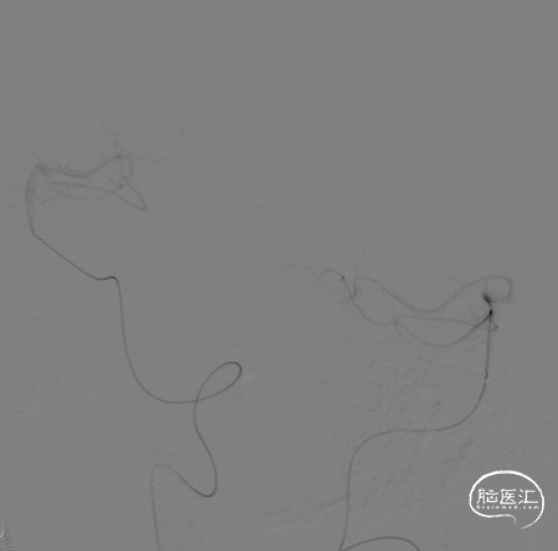

术中DynaCT。

术后4h CT。